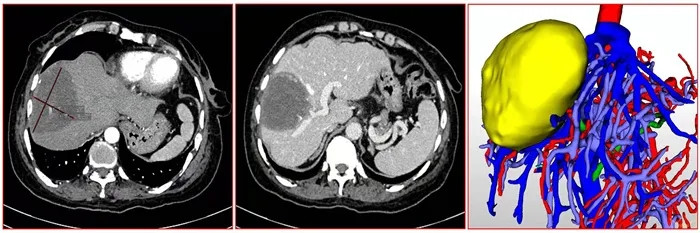

入院后肝胆外科经CT、核磁共振检查发现肝脏及盆腔有巨大肿块,考虑肝脏包虫病、盆腔包虫病或盆腔畸胎瘤的可能。因病灶与血管关系密切,盆腔肿块性质待定,需多学科联合会诊决定治疗方案。

肝脏包虫病灶